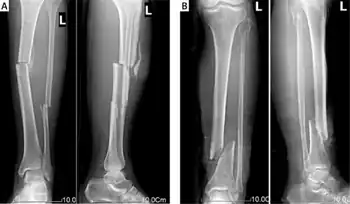

Combined tibia and fibula fracture

X-ray film of typical cases with open tibia and fibula fracture.

A tib-fib fracture is a fracture of both the tibia and fibula of the same leg in the same incident. Since the fibula is smaller and weaker than the tibia, a force strong enough to fracture the tibia often fractures the fibula as well. Types include: